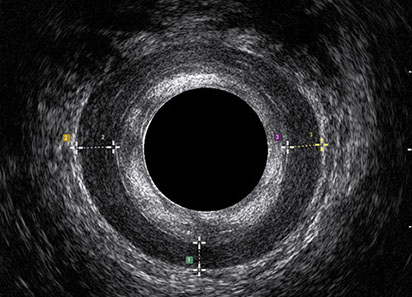

L’ecografia transanale è un esame diagnostico per immagini che consiste nell’introduzione di un trasduttore ad ultrasuoni. Le immagini qualitativamente migliori del canale anale sono ottenute usando un trasduttore rotante, montato in un manipolo rigido, che fornisce un’immagine a 360°. Con le apparecchiature più moderne è anche possibile ottenere immagini tridimensionali.

L’ecografia transanale permette di distinguere la sottomucosa che riveste il canale anale, lo sfintere anale interno, e lo sfintere anale esterno.

Proctal dispone di apparecchiatura per ecografia endoanale 3D con sonda rotante.